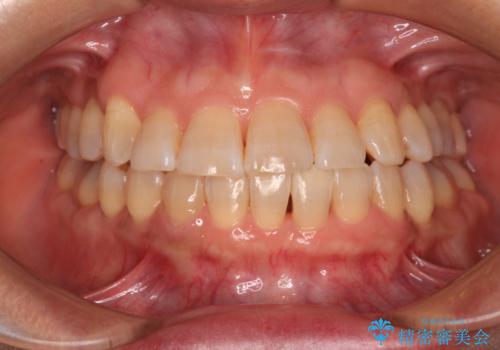

遠方から新幹線で通院 急速拡大装置とインビザラインによる矯正治療

- 小児矯正の頃から診察を行っている患者様です。

上顎骨の幅が下顎骨よりも小さいので、拡大装置により骨幅を広げて上下関係を改善し、その後インビザラインにて歯並びを整えることとしました。

上下の骨幅を改善したことで、スムーズに歯列矯正を行うことができました。

インビザライン治療開始直後に遠方に引っ越しをされたため、通院間隔が長くなり、治療期間が長くなりましたが、しっかりと治療を行うことができました。